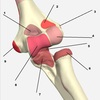

4

A

Flexor capri ulnaris

medial epicondyle (humerus) + olecranon -> pisiform/hamate/5th MC

flexion and adduction of the wrist

ulnar nerve